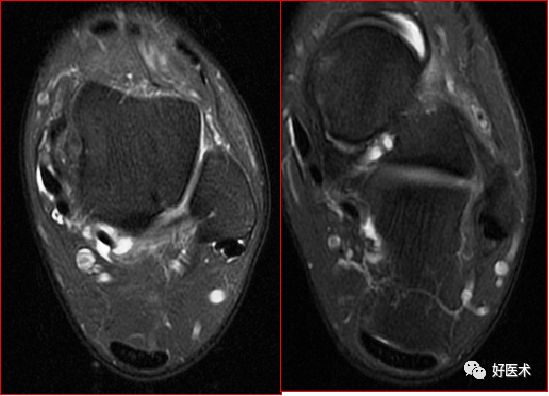

胫骨后肌肌腱撕裂